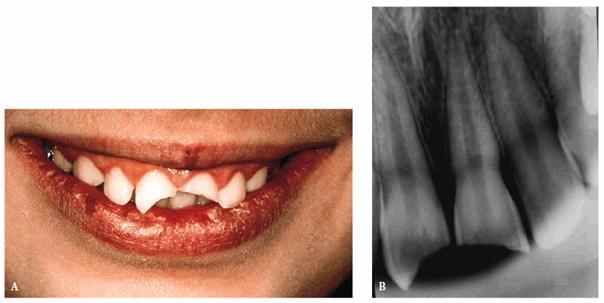

A female patient, 9 years, 2 months old.

PROBLEM: This patient presented with an extended, noncomplicated enamel

and dentin fracture of teeth #8 and #9. Four days had passed since the trauma

occurred, and the fragments had not been hydrated (Figures 27-6A

and B

Figure 27-6A and B: An extended but not complicated enamel and dentin fracture of teeth #8 and #9.

TREATMENT: After performing routine clinical, instrumental, and

radiographic examinations, it was decided to try to rehydrate the tooth

fragments by putting them in a physiologic saline solution for 1 day. In the

meantime, the fit of the tooth fragments was confirmed (Figures 27-6C

and D). The

following day, the two rehydrated tooth fragments had reached their normal

color, and the reattachment of the two fragments proceeded as described above.

Figure 27-6C and D: The tooth fragments have not been hydrated for 4 days. They fit perfectly but are discolored.

RESULT: The result obtained was much better functionally and

esthetically than it would have been using only composite resin. This

one-appointment procedure (due to a perfect fitting of the fragments) has restored

the anterior guide and has reached a correct reproduction of the biting edge (Figures 27-6E

and F

Figure 27-6E and F: The fragments have been rehydrated for 1 day and then reattached. The final result and the patient's smile are satisfying.

When

physiologic effects are more important than cosmetic ones; this technique

allows a "true biological restoration" with a true "restitutio

ad integrum" of the tooth crown. No additional treatment has been required

on the teeth other than periodic examinations.